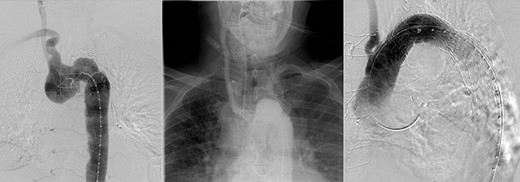

A 78-year-old male presented with sudden onset tearing chest pain with radiation to the back and associated dyspnoea and dysphagia. This was on a background of ischaemic heart disease, hypertension, hypercholesterolaemia and previous small bowel resection for neuroendocrine mesenteric malignancy. He was an ex-smoker with no personal or family history of connective tissue disorders. On computed tomography angiography (CTA) he was found to have an aberrant right subclavian artery (SCA), coursing posterior to the trachea and oesophagus, with an associated 4.4 cm Kommerell’s diverticulum (Fig. 1). Imaging also illustrated tracheal stenosis and oesophageal compression. A coronary angiogram demonstrated severe double vessel coronary artery disease. A staged procedure with aortic arch debranching and coronary artery bypass grafting (CABG), followed by a thoracic stent graft and amplatzer plug to address the Kommerrel’s Diverticulum was planned.

Computed tomography (CT) reconstruction illustrating Kommerell’s diverticulum and an aberrant right subclavian artery.

CT reconstruction illustrating a debranched left common carotid artery and subclavian artery with double coronary artery bypass graft (left internal mammary artery to left anterior descending, and saphenous vein T graft to obtuse marginal artery).

The initial procedure, performed via a median sternotomy, involved debranching the left common carotid artery (CCA) and left SCA with simultaneous double vessel CABG (left internal mammary artery to left anterior descending, and saphenous vein T graft to obtuse marginal artery) (Fig. 2). This provided a sufficient landing zone for a thoracic aortic stent graft. His post-operative recovery was complicated by atrial fibrillation, hospital acquired pneumonia and delirium requiring reintubation for severe agitation. The patient was discharged home following rehabilitation with a plan to perform the second stage of the repair as a semi-elective procedure.